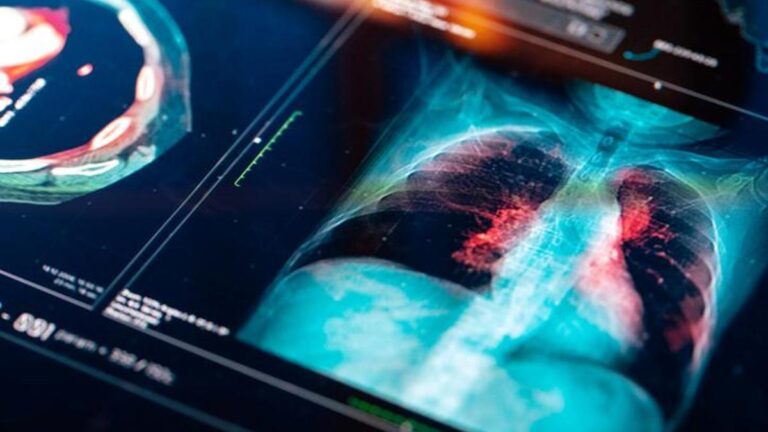

Bu nedenle, düşük dozaj akciğer tomografisinin bu anlamda önemli bir yeri vardır. Özellikle erken tomografi ile gerekli tedavi yöntemleri daha etkili olabilir. Ek olarak, kan testleri ve açıklık testleri de pulmoner kanser açısından tartışılmaktadır. Bu nedenle, gerekli tanılarda tartışılan yöntemler birden fazla şekilde kullanılır ve sonuç dahil edilir.